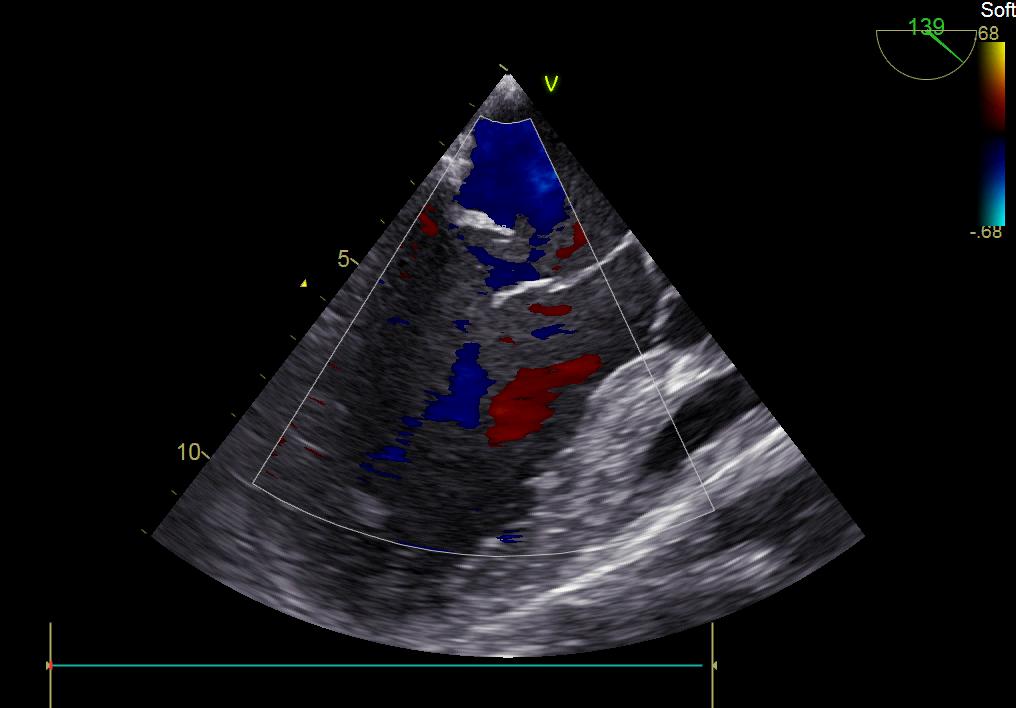

術(shù)前彩超